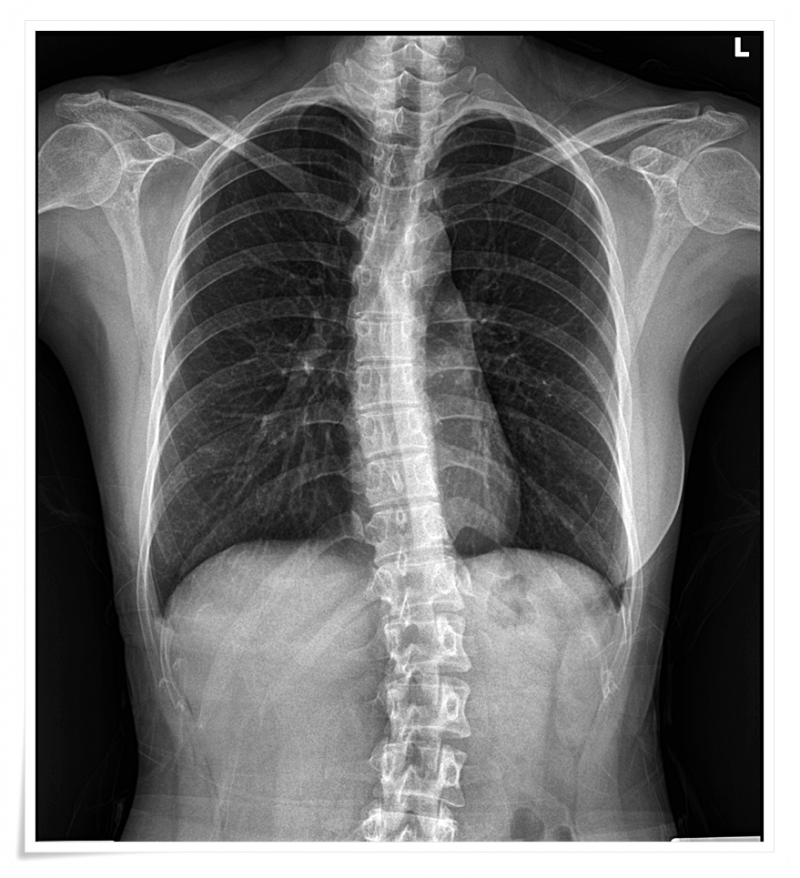

Q. 허리 디스크? 진짜 원인은 어디에 있을까요?

많은 분들이 허리 자체만 문제라고 생각하시지만,

실제로 진료를 하다 보면 그렇지 않은 경우가 더 많습니다.

골반과 관절의 균형이 무너지게 되면

척추 역시 자연스럽게 불균형 상태가 되는데요.

과정에서 주변 근육과 조직은

과도한 긴장 상태에 놓이게 되고,

신경이 자극되면서 통증이 시작됩니다.

골반·척추·하지의 연결 구조를 함께 살펴봅니다.

겉으로는 허리 통증이 심해 보이지만,

실제로는 골반의 미세한 틀어짐이

원인인 경우도 적지 않기 때문입니다.